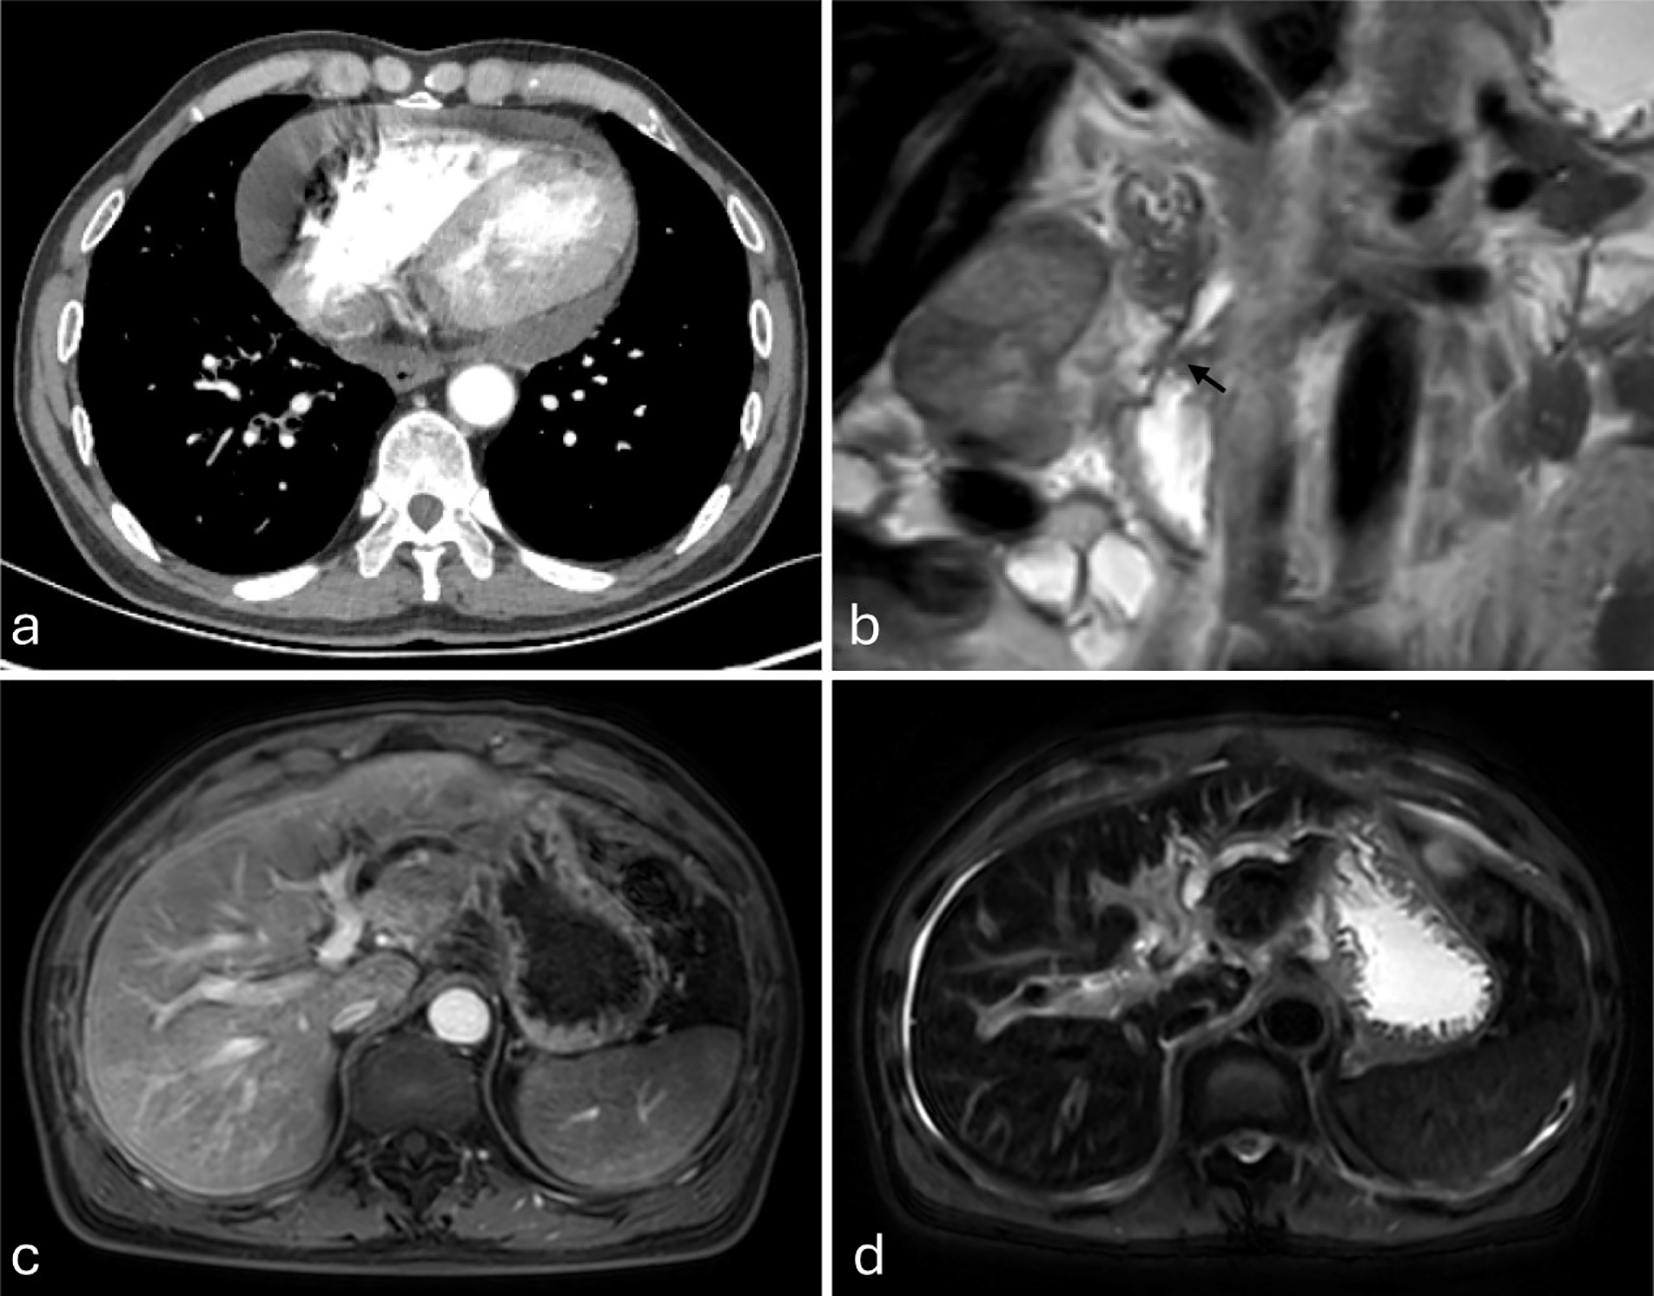

Figure 2

(a–d) Imaging studies from an external institution (December 5, 2024). (a) Contrast-enhanced chest CT demonstrates pericardial effusion. (b–d) Magnetic resonance imaging (MRI), (b) Coronal T2-weighted imaging (T2WI) clearly demonstrates tapered stenosis at the distal common bile duct and pancreatic duct orifice (marked by black arrows). (c) Axial fat-suppressed contrast-enhanced T1-weighted imaging (T1WI) shows intrahepatic biliary dilatation in the left hepatic lobe. (d) Axial fat-suppressed T2WI demonstrates left hepatic lobe intrahepatic biliary dilatation and ascites.